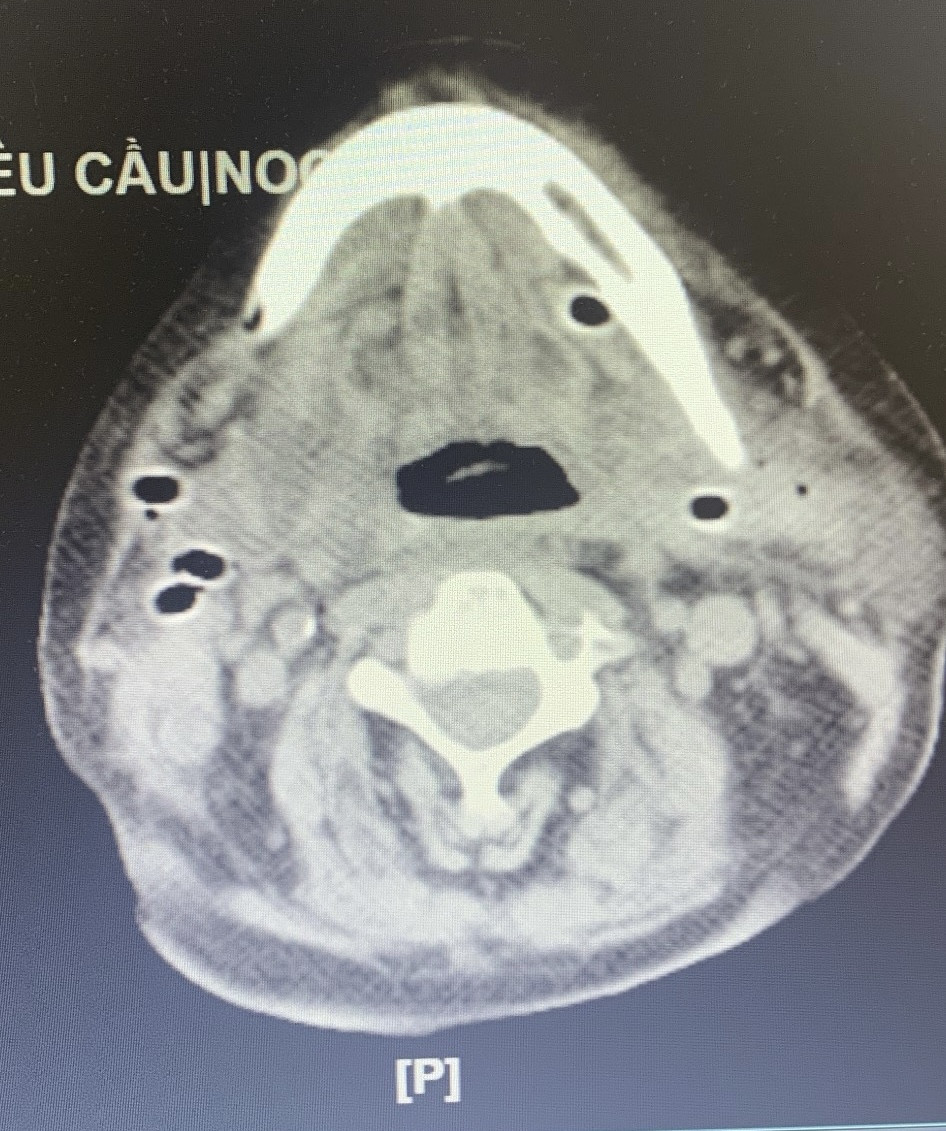

Thời điểm nhập Bệnh viện Việt Đức, ông T. khó thở nhiều, vết mổ chảy nhiều dịch mủ hôi. Người bệnh được làm xét nghiệm chụp cắt lớp với chẩn đoán bệnh viêm tấy sàn miệng lan tỏa do răng và phải mổ cấp cứu.

Khi rạch vùng dưới hàm của người bệnh, bác sĩ rút ra hàng trăm ml mủ, ổ mủ thông vào khoang miệng, lan xuống vùng cổ và có nguy cơ lan trung thất nếu không được xử lý kịp thời.